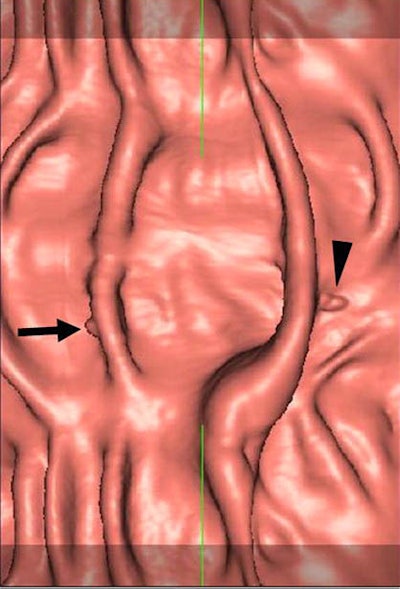

| Software-generated supine (above) and prone (below) 3D virtual dissection images. Each 10° area at the top and bottom of the image is added to the full 360° view of the colonic surface and displayed with a transparently shaded color so as not to miss any lesion. The colonic surface can be observed quickly by using the top scroll bars. Note that the polyp (arrows) remains unchanged on both images, but the lump of feces (arrowheads) changes in position. A 5-mm adenomatous polyp was confirmed at both colonoscopy and biopsy. Images (Fig. 1c) republished with permission of the authors and the Radiological Society of North America from Se Hyung Kim, M.D.; Jeong Min Lee, M.D.; Hyo Won Eun, M.D.; Min Woo Lee, M.D.; Joon Koo Han, M.D.; Jae Young Lee, M.D.; and Byung Ihn Choi, M.D.; "Two- versus Three-dimensional Colon Evaluation with Recently Developed Virtual Dissection Software for CT Colonography," Radiology 2007;244:852-864, © RSNA 2007. |